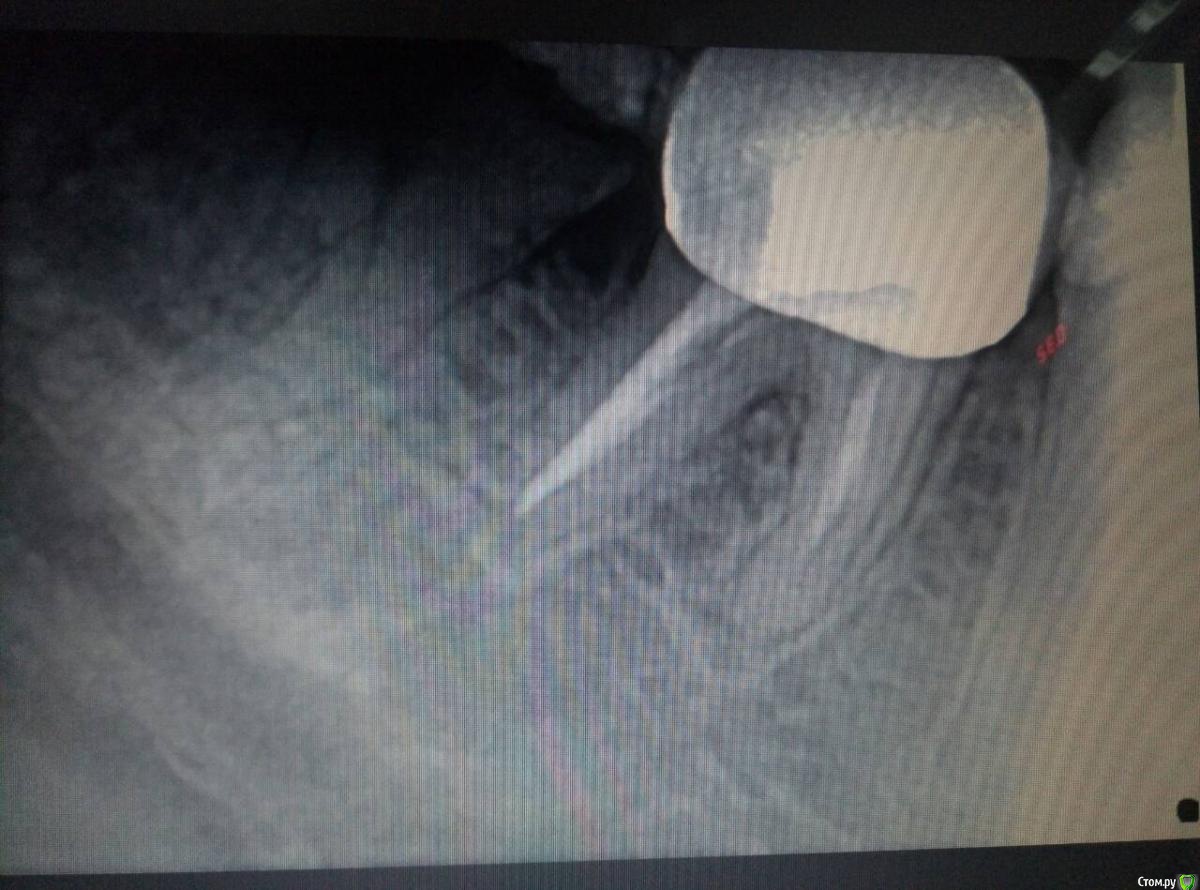

Инна2106 Опубликовано 27 июля, 2018 Поделиться Опубликовано 27 июля, 2018 (изменено) Добрый день.Прошу помочь определить в чем может быть причина ситуации с зубом которая длиться уже две недели.Началось все в ночь 13 августа проснулась от боли в одном участке нижней челюсти, именно не зубе, а челюсти, боль не острая, а тупая ноющая. Встала, походила все прошло. Весь день ничего не болело. В ночь все повторилось уже дважды просыпалась от боли, не определенного зуба, а низа левой челюсти. Для снятия боли достаточно было просто походить в течении 5 минут, все успокаивалось.На следующий день пошла к врачу, сделал снимок, осмотрел, сказал, что есть небольшая гранулема под шестым зубом под коронкой из-за не до конца запломбированного канала, но это как оказалось старая проблема, определялась еще на ортопанораме зимой. Но по его словам она не может давать такого рода болей. Ночью не спала вообще, четыре раза вставала от болей, причем стоило только принять горизонтальное положение и начиналась ноющая боль в нижней челюсти слева, и потом верхней челюсти слева. Суть в том что боли появлялись именно когда ложилась, не важно днем или ночью, пока ходишь, сидишь ничего не беспокоило. Снова поехала на прием к врачу, сделал много проб, и воздухом и нитью, подозревал трещину по снимку рядом в зубе под пломбой, но сказал нить не цепляется и не рвется значит ее нет, но вскрывать этот зуб не смысла так как на простукивание все было спокойно и сверху и снизу. Десна все розовые, кровоточивости нет. Через три дня поехала к другому врачу сделал свой снимок, предположил как вариант что восьмерка может двигать зубной ряд оттуда и боль, но сама восьмерка абсолютно спокойна, не болит, нет отечности десны. Его заключение, что причина в троичном нерве, а не в зубах. До этого по рекомендации первого врача принимала Азитромицин 3 дня и Нимесил не помогло. Начала пить Нейродикловит (диклофенак с витаминами группы В) и наконец-то начала ночью спать, но с понедельника 23 июля начал болеть зуб при накусывании рядом с коронкой (семерка), я на эту сторону и так не ем уже две недели, почувствовала боль при пережевывании пищи. когда верхних зуб попадал на нижний, попробовала постучать ложкой и ощутила боль в семерке снизу. В среду поехала к третьему врачу, он сделал пришлифовку семерки нижней с верхней так как нагрузка на зуб неправильно распределялась на одно сторону, порекомендовал попить Нимесил и наблюдать.Суть в том, что на данный момент исчезли боли в горизонтальном положении, но не могу жевать и есть нормально, сам зуб не болит, но если попробовать накусить слегка зубочистку на семерку появляется боль, отпускаешь проходит.Очень прошу помогите разобраться что это и как себе помочь, скоро нужно уезжать и не знаю стоит ли сейчас снимать коронку или все же причина не в этом зубе. Стоит ли делать КТ, новую ортопанораму, если по снимкам ничего не видят. Внизу прикрепила фрагмент ортопанорамы делала в феврале этого года, и нашла снимок этого сделанный в конце апреля прошлого года для сравнения.Заранее большое спасибо. Изменено 27 июля, 2018 пользователем Инна2106 Ссылка на комментарий

Инна2106 Опубликовано 27 июля, 2018 Автор Поделиться Опубликовано 27 июля, 2018 Еще снимок Ссылка на комментарий